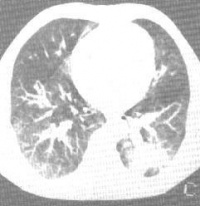

X线检查:肿瘤极小时可阴性。近肺门的支气管腺瘤,可呈圆形或半圆形阴影;位于肺脏周围部者,呈结节状或球形影。可伴阻塞性肺气肿,肺不张,阻塞性肺炎,甚至肺脓肿,肿瘤有时被掩盖。

支气管腺瘤发病年龄较轻,常有较长时间的呛咳、咯血及反复肺部感染胸部X线征象呈圆形致密阴影。尤其是分层摄影和CT扫描可清晰地显示肿瘤的部位、形态、大小、支气管阻塞情况及有无区域淋巴结转移。支气管镜检查是诊断本病的重要方法之一,不仅能确定肿瘤部位,且可活检提供病理学诊断。纤维支气管镜活检阳性率可达66%~86%。由于肿瘤富含血管,且表面有完整粘膜上皮覆盖,故要提高确疹率,必须重复作深部活检,但应防止出血;而痰脱落细胞、支气管冲洗及刷检物涂片检查对本病诊断无帮助。